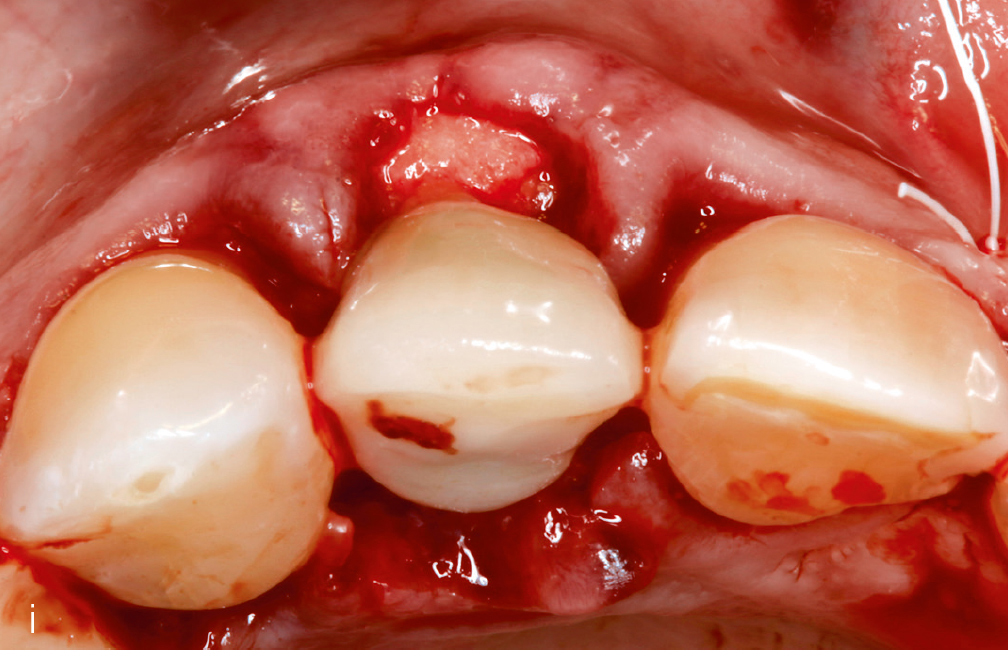

Abb. 3i bis m Falldokumentation mit Zustand nach Implantation und lateraler Augmentation alio loco: i) okklusale Ansicht mit eingebrachtem BGT vestibulär in der Region 12; j) Wundverschluss mit Naht; k) klinische Situation 9 Monate post operativ; l) okklusale Ansicht; m) klinische Parameter.